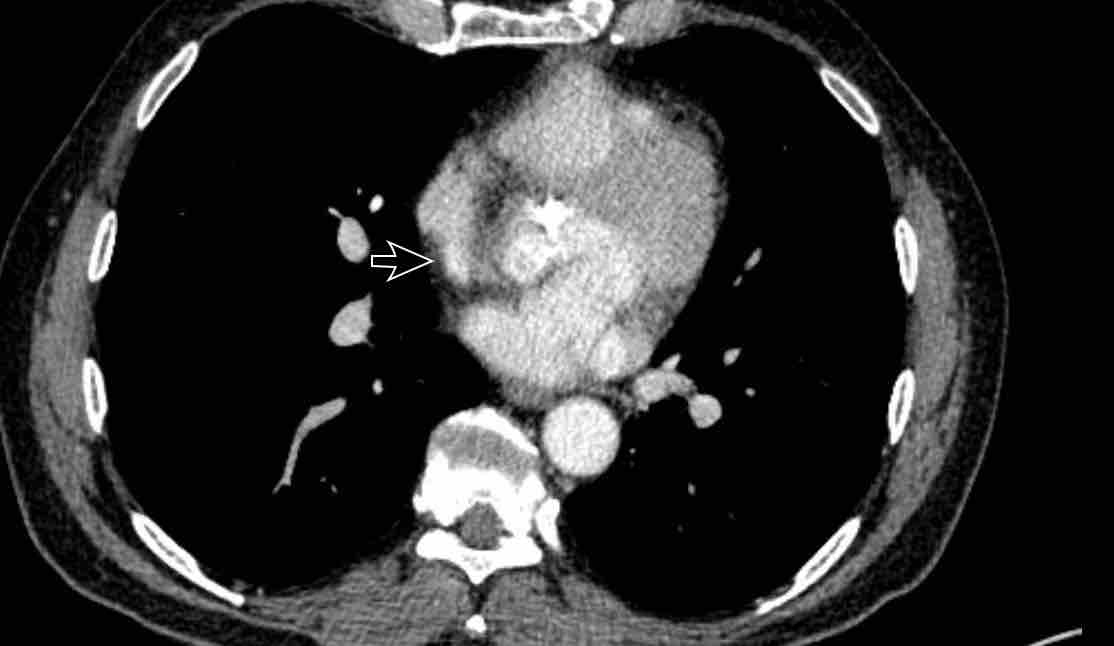

PAPVR bên trái phát hiện tình cờ với dẫn lưu trên tim của máu từ thùy trên trái vào tĩnh mạch tay đầu trái (các mũi tên).